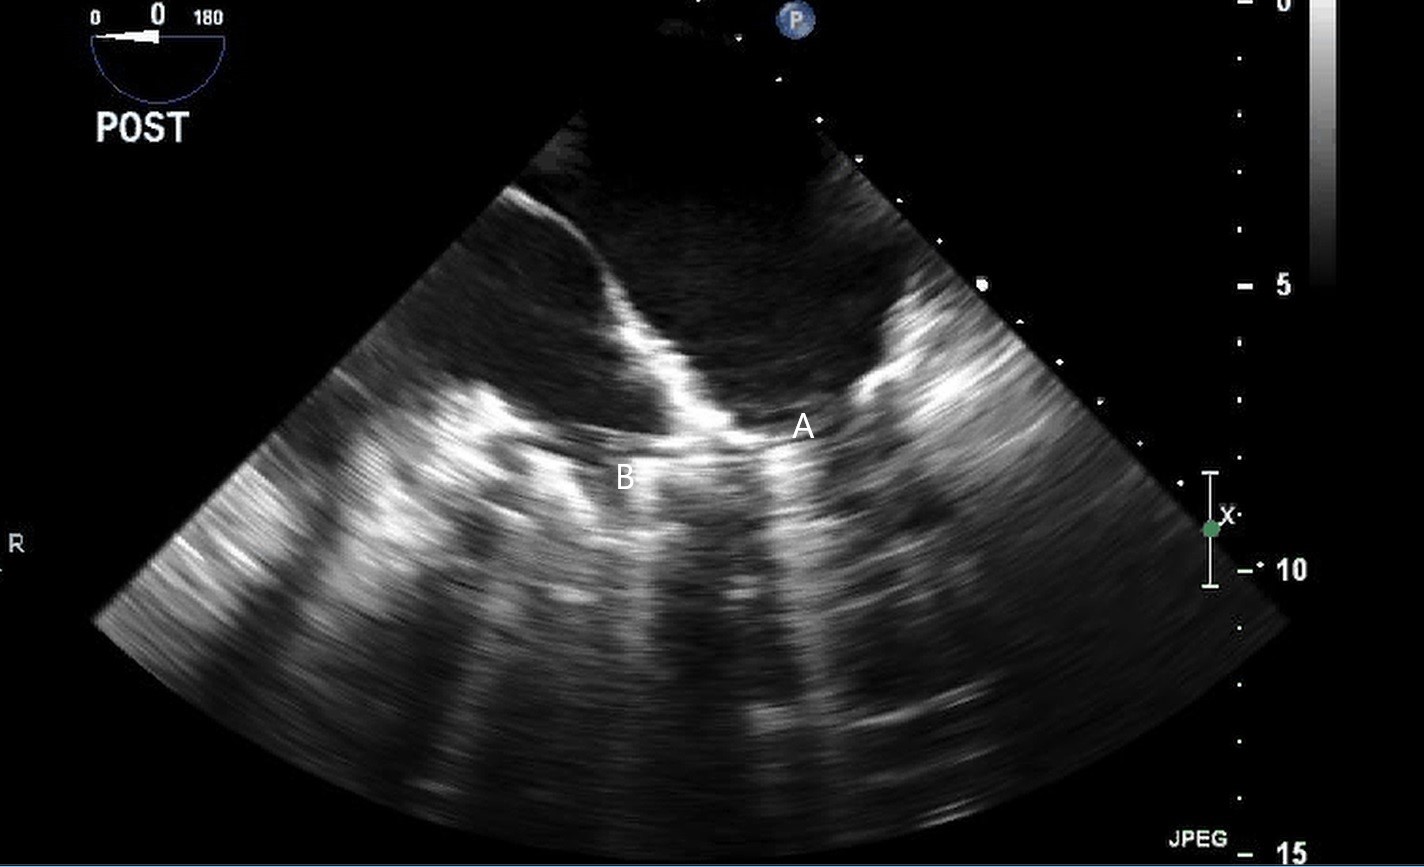

When examining the inflow cannula of the LVAD, the inflow cannula should be orientated and aligned with the mitral valve [47] (Figs. 19,20). Laminar flow from the ventricle to the device suggests a correctly aligned inflow cannula [56]. Obstruction of the inflow cannula manifests with increased turbulence and elevated doppler velocities [47].

Fig. 19.Transthoracic echocardiogram PLAX image demonstrating inflow cannula at LV apex (A) and AV systolic closure (B).

Fig. 20.Transesophageal echocardiogram four chamber image with the LVAD inflow cannula pointing towards the septum (A). (B) LV (C) LA.